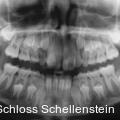

Gemination im Frontzahnbereich: Zahntransplantation als Therapieoption